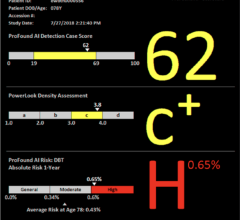

The algorithms that will be developed to obtain the medical images will offer two types of images simultaneously: the image of the patient's tissue, and the image of its associated uncertainty, which shows, pixel by pixel, how reliable the information is. The project also incorporates concepts such as multimodal imaging and real 3D imaging, which is an unprecedented combination in ultrasound breast imaging.

Mammography is one of the most widely used methods to detect breast cancer and has saved millions of lives. However, there are studies that claim that it can give false positives and alert of a possible tumor that is not found later in the screening phase.